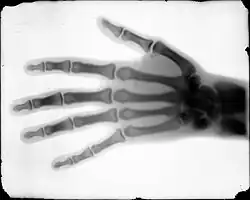

X-ray of the hand of Dr. Tennant taken by Buckwalter

In 1895, Buckwalter took interest in X-ray technology, after its discovery by professor Wilhelm Röntgen earlier that year. Sponsored by the Rocky Mountain News, Buckwalter partnered with physician C. E. Tennant and the Homeopathic Medical College of Denver on a series of X-ray photograph experiments. For the experiment Buckwalter produced X-ray tubes locally using leaded glass which was previously thought to be unsuitable, but the experiment proved that leaded tubes could produce a clear image.[6] The X-ray images were the first produced in the American West and among the earliest in the country.[1][7]